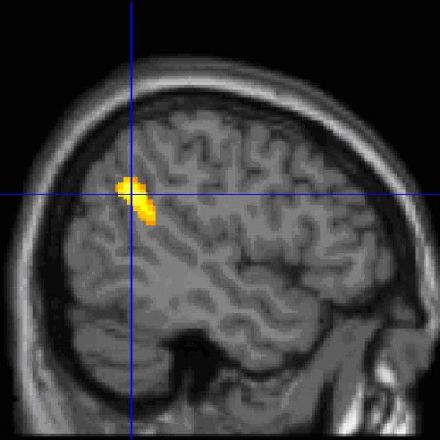

Some people recall a dream every morning, whereas others rarely recall one. In a new study, research shows that the temporo-parietal junction, an information-processing hub in the brain, is more active in high dream recallers. Increased activity in this brain region might facilitate attention orienting toward external stimuli and promote intrasleep wakefulness, thereby facilitating the encoding of dreams in memory.